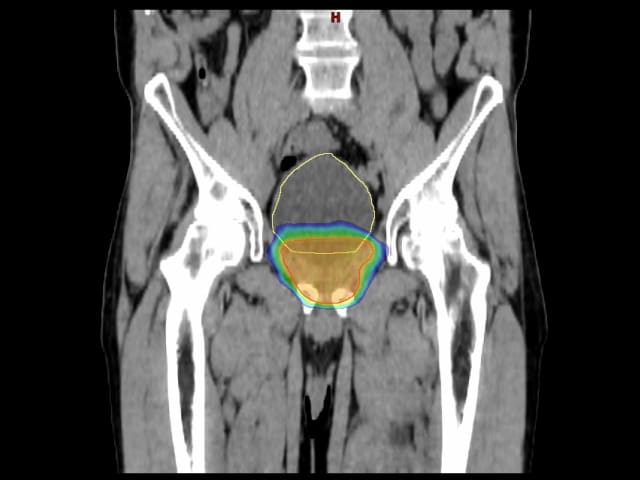

image

Bei Hinweisen auf eine erneute Tumoraktivität nach einer erfolgten Prostataentfernung, wird meist eine Bestrahlung des Orts, wo zuvor die Prostata gelegen hatte, vorgenommen. Rote Linie: Zielvolumen für die Betrahlung. Gelbe Linie: Harnblase. Farbige Fläche (von Blau bis Orange): Abstufung der Bestrahlungsdosis (Bild: Insel Gruppe)